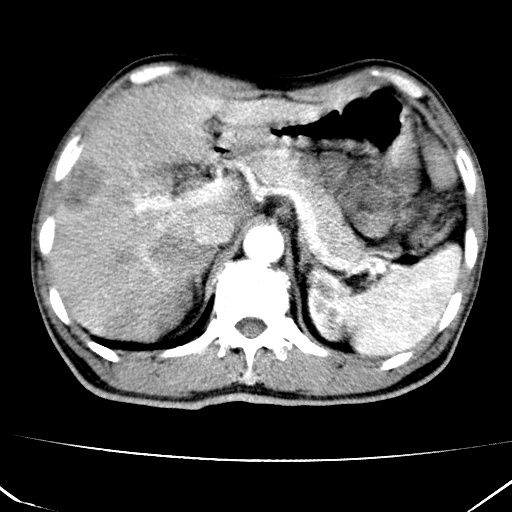

标题: CT17975:请求会诊。男、57岁。上腹部胀痛2天。临床诊断:糜 [打印本页]

标题: CT17975:请求会诊。男、57岁。上腹部胀痛2天。临床诊断:糜

肝脏多发类圆形低密度影,考虑肝脏转移瘤,肝胃韧带一淋巴结肿大,原发?胃癌?

考虑胃癌并肝脏及腹膜后淋巴结转移;不排除淋巴瘤。

肝内转移瘤,腹腔及腹膜后淋巴结转移。